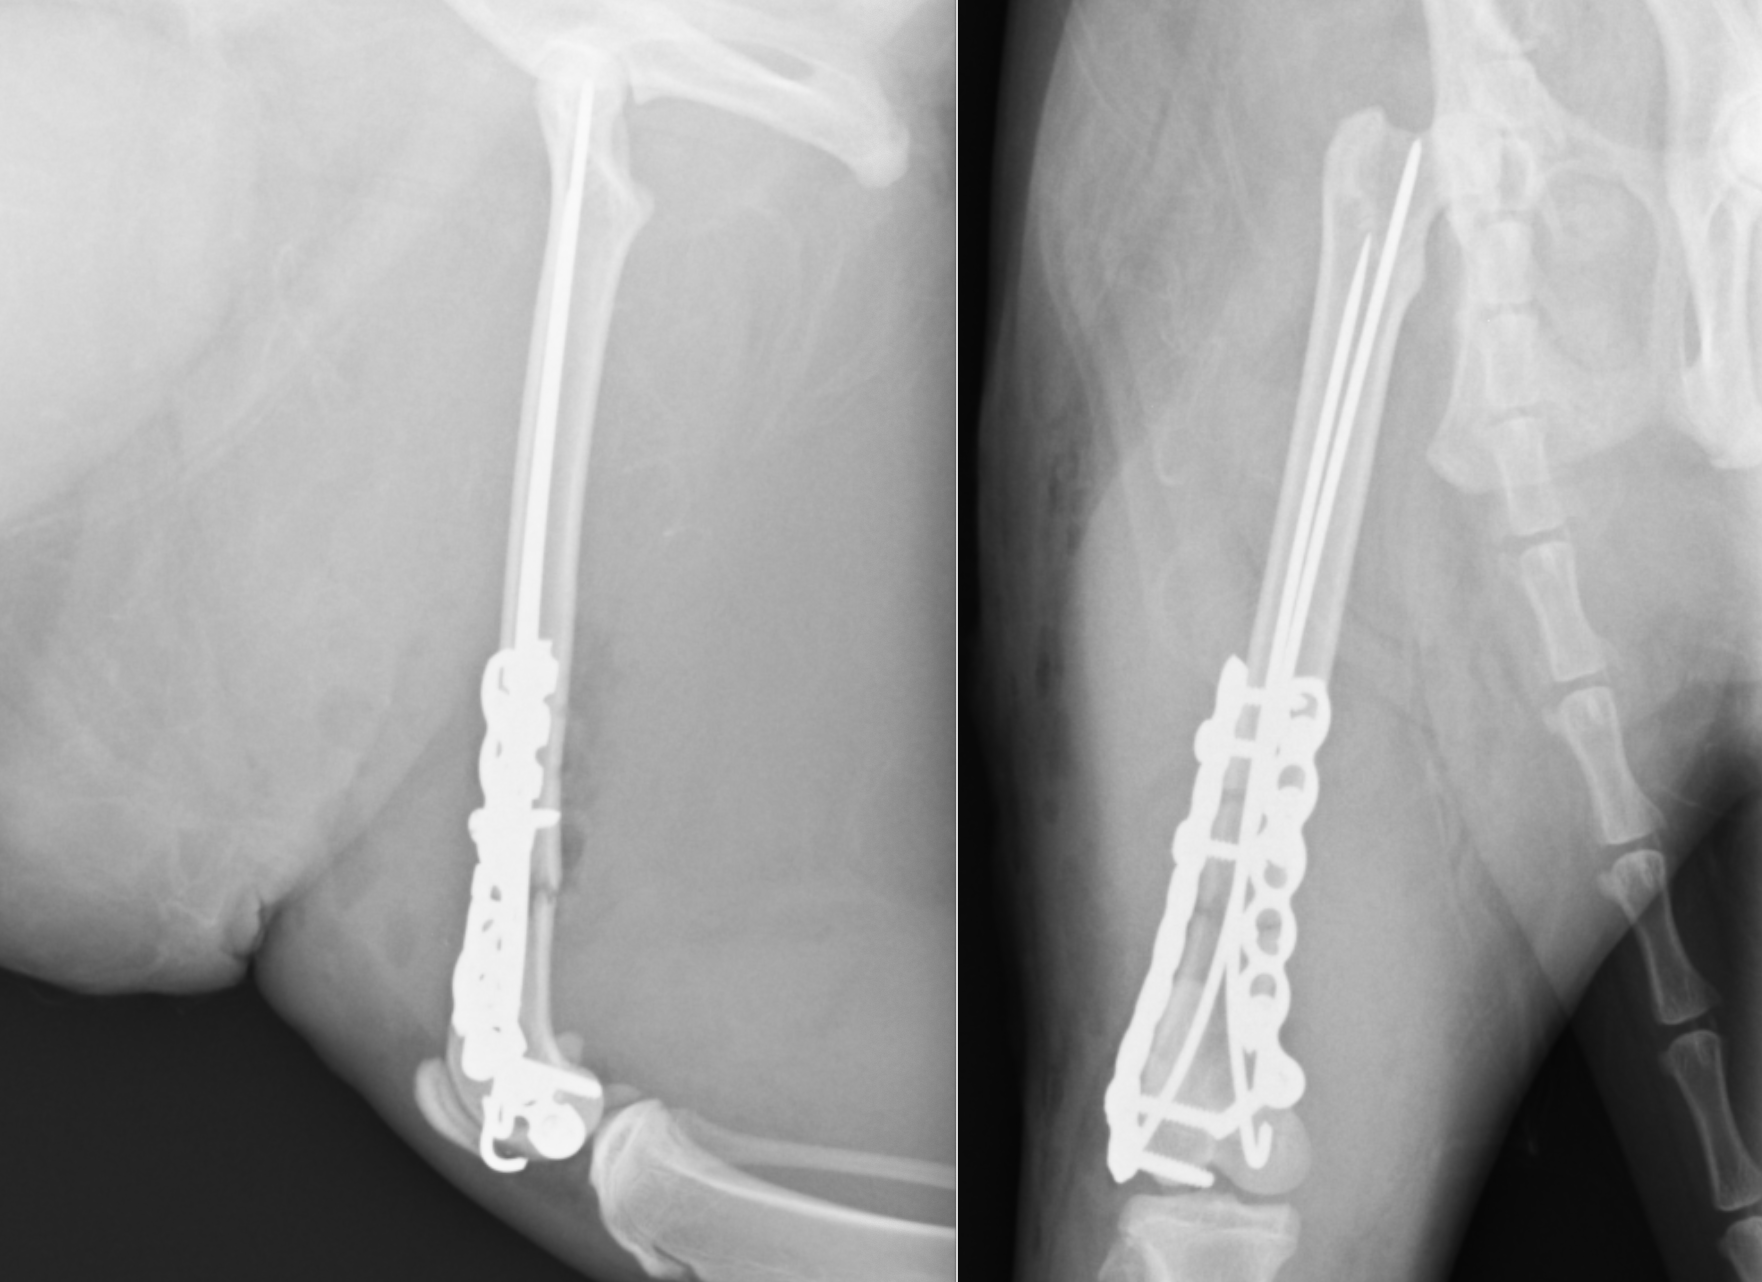

今回は術後2ヶ月ほどでプレートとピンを一部抜去しインプラントの強度を弱めました。ココまでくればもう通常通りの生活に戻ることが可能です。